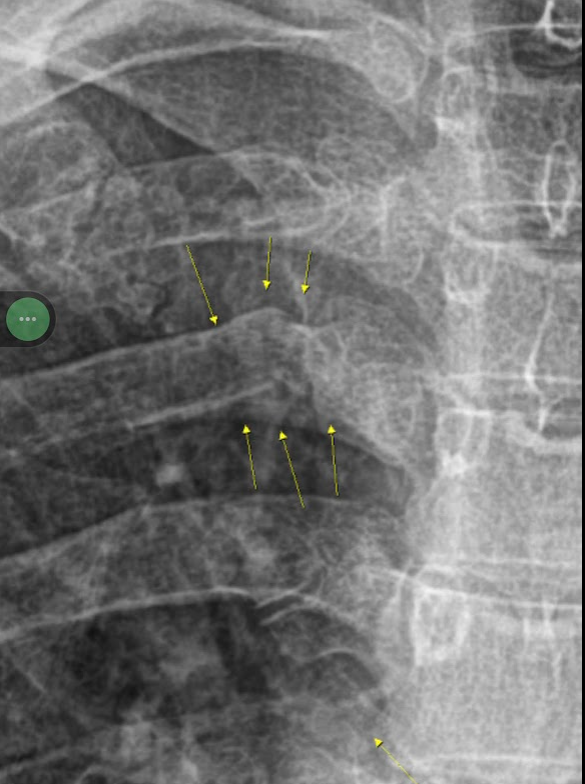

벌써 한 달 전 얘기입니다만, 갈비뼈가 부러졌습니다. 자전거 때문에요. 자전거 때문이라 하면, 타다가 넘어졌나보다 생각하기 쉬운데, 전혀 생각지도 못한 이유 때문이었습니다. https://www.dwnc.me/10 서재 리뉴얼 (221124-29) 발디딜 틈이 없다 컴퓨터, 스마트로라, 금고, 자전거 등을 비롯해 얼마 전 거실에서 쫓겨난 워킹패드까지.. 온갖 잡다한 물건들이 입주해 있는 서재 모습입니다. 이 지경이 되니, 방에 잘 안들어 www.dwnc.me 지난 11월에 했던 서재 리뉴얼 이후로도 방 배치를 몇 번 더 바꾸었습니다. 그러다 보니 실내용 자전거를 로라에 떼었다 얹었다도 자주 반복하게 되었죠. 'QR 레버 방식'으로 바퀴를 고정하는 자전거는 로라에 얹을 때 주의할 점이 있는데요. 프레임 아..